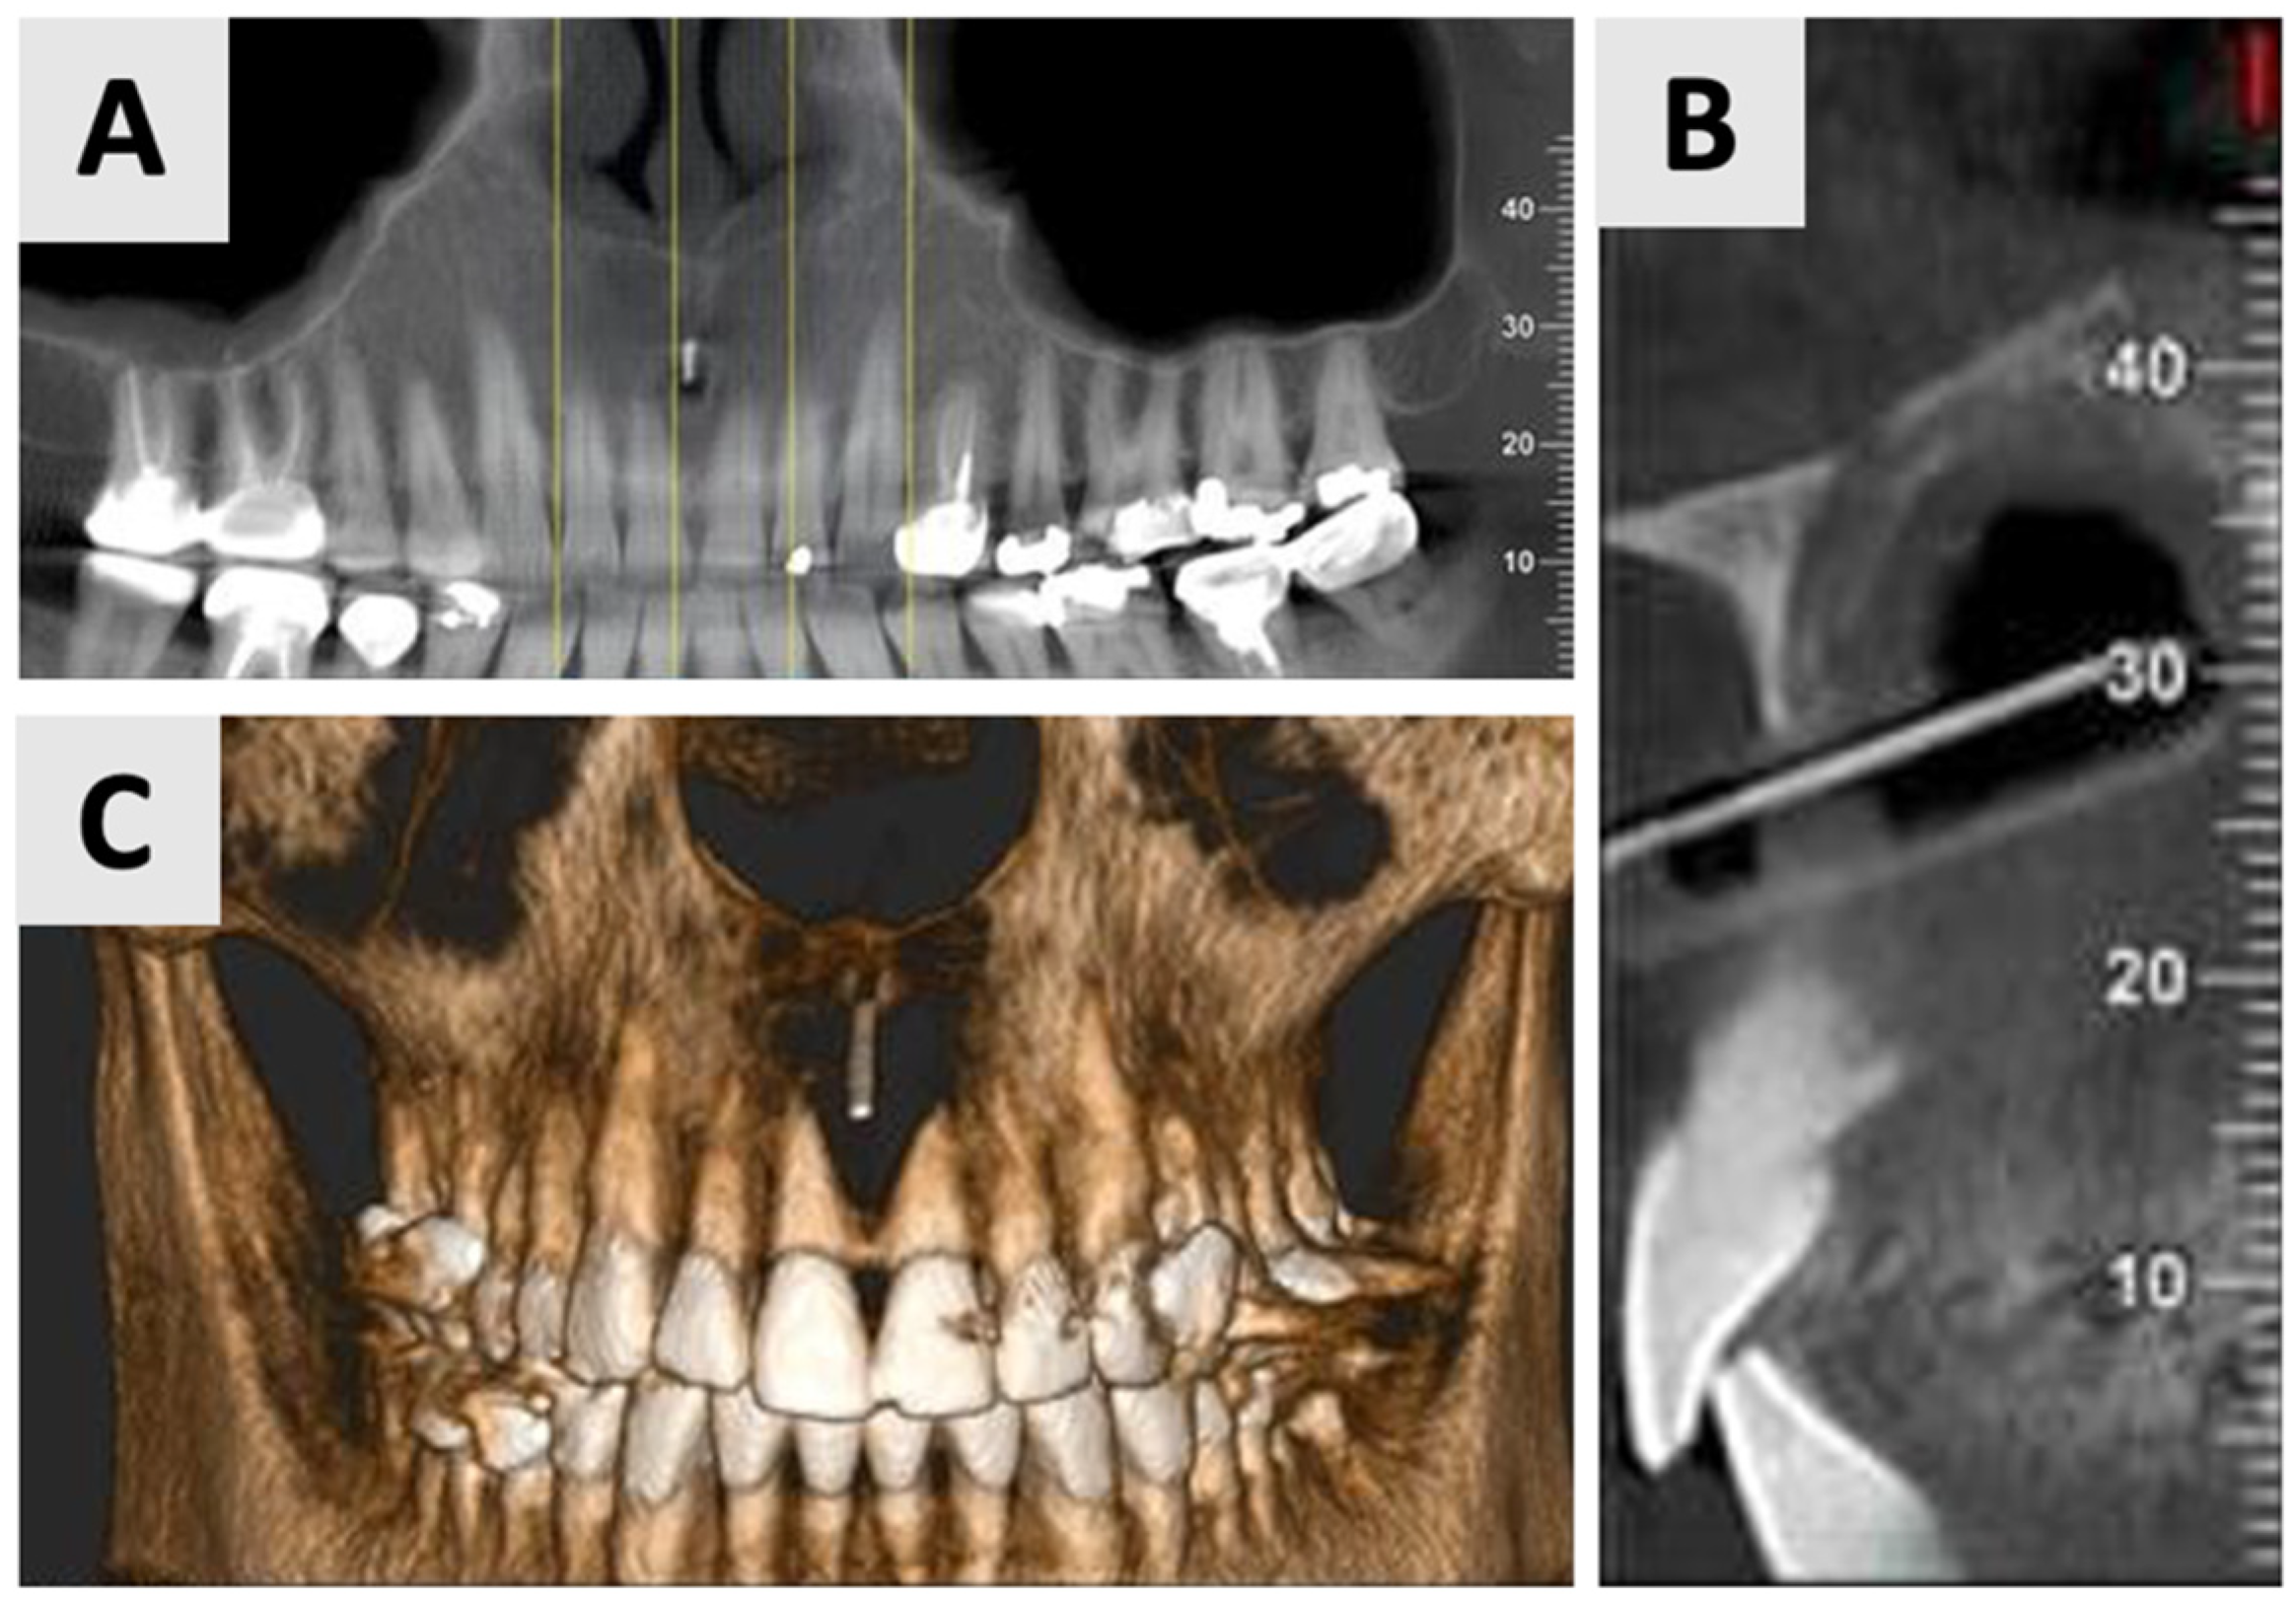

Due to the size and anatomical location of the cyst (Figure 1), a marsupialization approach was selected as the preferred treatment strategy. A small incision was made for initial biopsy and drainage of the cystic fluid, followed by thorough irrigation with sterile normal saline to cleanse the site. The cystic lining margins were carefully sutured using 3-0 VICRYL® RAPIDE (polyglactin 910) sutures (Ethicon, Johnson & Johnson Medical Technologies, Cincinnati, OH, USA) to the adjacent gingival mucosa to create a continuous epithelial-lined cavity, preventing premature closure. A rubber drain was placed to ensure continuous decompression and facilitate the gradual evacuation of residual fluid, controlling shrinkage of the lesion. The patient was instructed to perform cyst irrigation via the rubber drain three times daily. A structured follow-up protocol was implemented, comprising weekly visits for the initial four weeks, followed by a six-week assessment. Antibiotic prophylaxis consisted of Amoxicillin 500 mg (Teva Pharmaceuticals Industries Ltd., Petah Tikva, Israel) administered three times daily for one week. To control analgesia, a nonsteroidal anti-inflammatory drug Etodolac® 400 mg (Taro Pharmaceuticals, Haifa, Israel) was prescribed up to three times daily. To minimize infection risk, chlorhexidine 2% (Tarodent® 0.2% Chlorhexidine Gluconate Oral Rinse, Taro Pharmaceutical Industries Ltd., Haifa, Israel) oral rinses were recommended three times daily for one week. The histopathological analysis, completed three weeks post-procedure, showed a diagnosis of inflamed non-keratinizing odontogenic cyst. At the six-month mark, the patient requested a revision of the treatment plan due to the prolonged duration of therapy and changes in personal circumstances. Therefore, an evaluation was performed, including clinical assessment and radiographic analysis (Figure 2).

Figure 2.

Radiographic evaluation of cyst six months following marsupialization. (A) Panoramic reconstruction illustrating the initial defect site prior to enucleation. (B) Cyst regression and improved bone density in the affected area. (C) Paraxial view.

The findings indicated favorable cyst regression and improved bone density in the affected area. Based on these results, it was determined that the marsupialization had created optimal conditions for the next phase of treatment. Consequently, the decision was made to proceed with cyst enucleation, marking the transition to the definitive surgical management of the lesion.

The surgical phase of cyst enucleation (Figure 3) was initiated following the six-month marsupialization period. Local anesthesia was administered using Cook-Waite® Lidocaine HCl 2% and Epinephrine 1:100,000 Injection (Septodont, Saint-Maur-des-Fossés, France). The surgical approach began with intrasulcular incisions extending from the right to left maxillary canines. These were complemented by vertical releasing incisions at the transitional line angles of both maxillary canines, facilitating optimal flap design and access (Figure 3C). A full thickness mucoperiosteal flap was elevated, exposing the bony architecture and revealing the entry point of the previously placed rubber drain (Figure 3D).

Figure 3.

Clinical stages of cyst management and removal. (A) Intraoral view showing the rubber drain in situ just before the end of marsupialization. (B) Palatal view demonstrating resolution of palatal swelling. (C) Surgical flap design with intrasulcular incisions from right to left maxillary canines and vertical releasing incisions at the transitional line angles. (D) Intraoperative view after full thickness mucoperiosteal flap elevation, revealing the bony entry point of the rubber drain. (E) Clinical view of the completely enucleated cyst specimen.